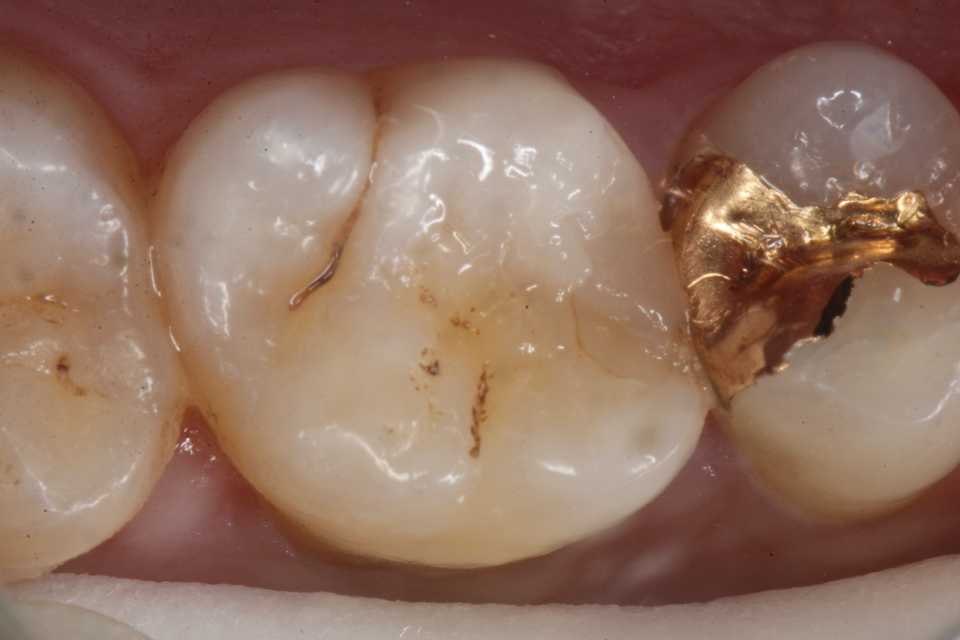

30代男性、右上6、隣接面カリエス、CR充填後(当院ではない)の2次カリエス、外傷性咬合(食いしばり)有り

ストレスフルな生活をされているようで、食いしばりがひどい。

今日は、10ヶ月程前に時間がないのでα-TCPで仮充填しておいた歯の治療の続き。

とりあえずα-TCPを除去し始めたが内部の象牙質は硬化している。虫歯はα-TCPで治る。

では時系列でどうぞ

頬側の虫歯は追求するしかない。